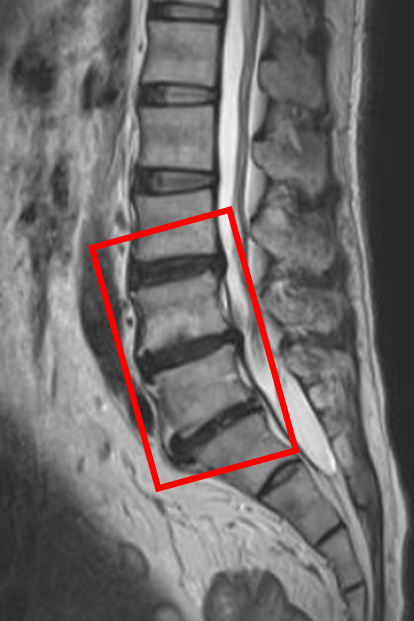

この患者様は赤い枠で示されている箇所(L3/4,4/5,5/s)に椎間板変性を認めます。